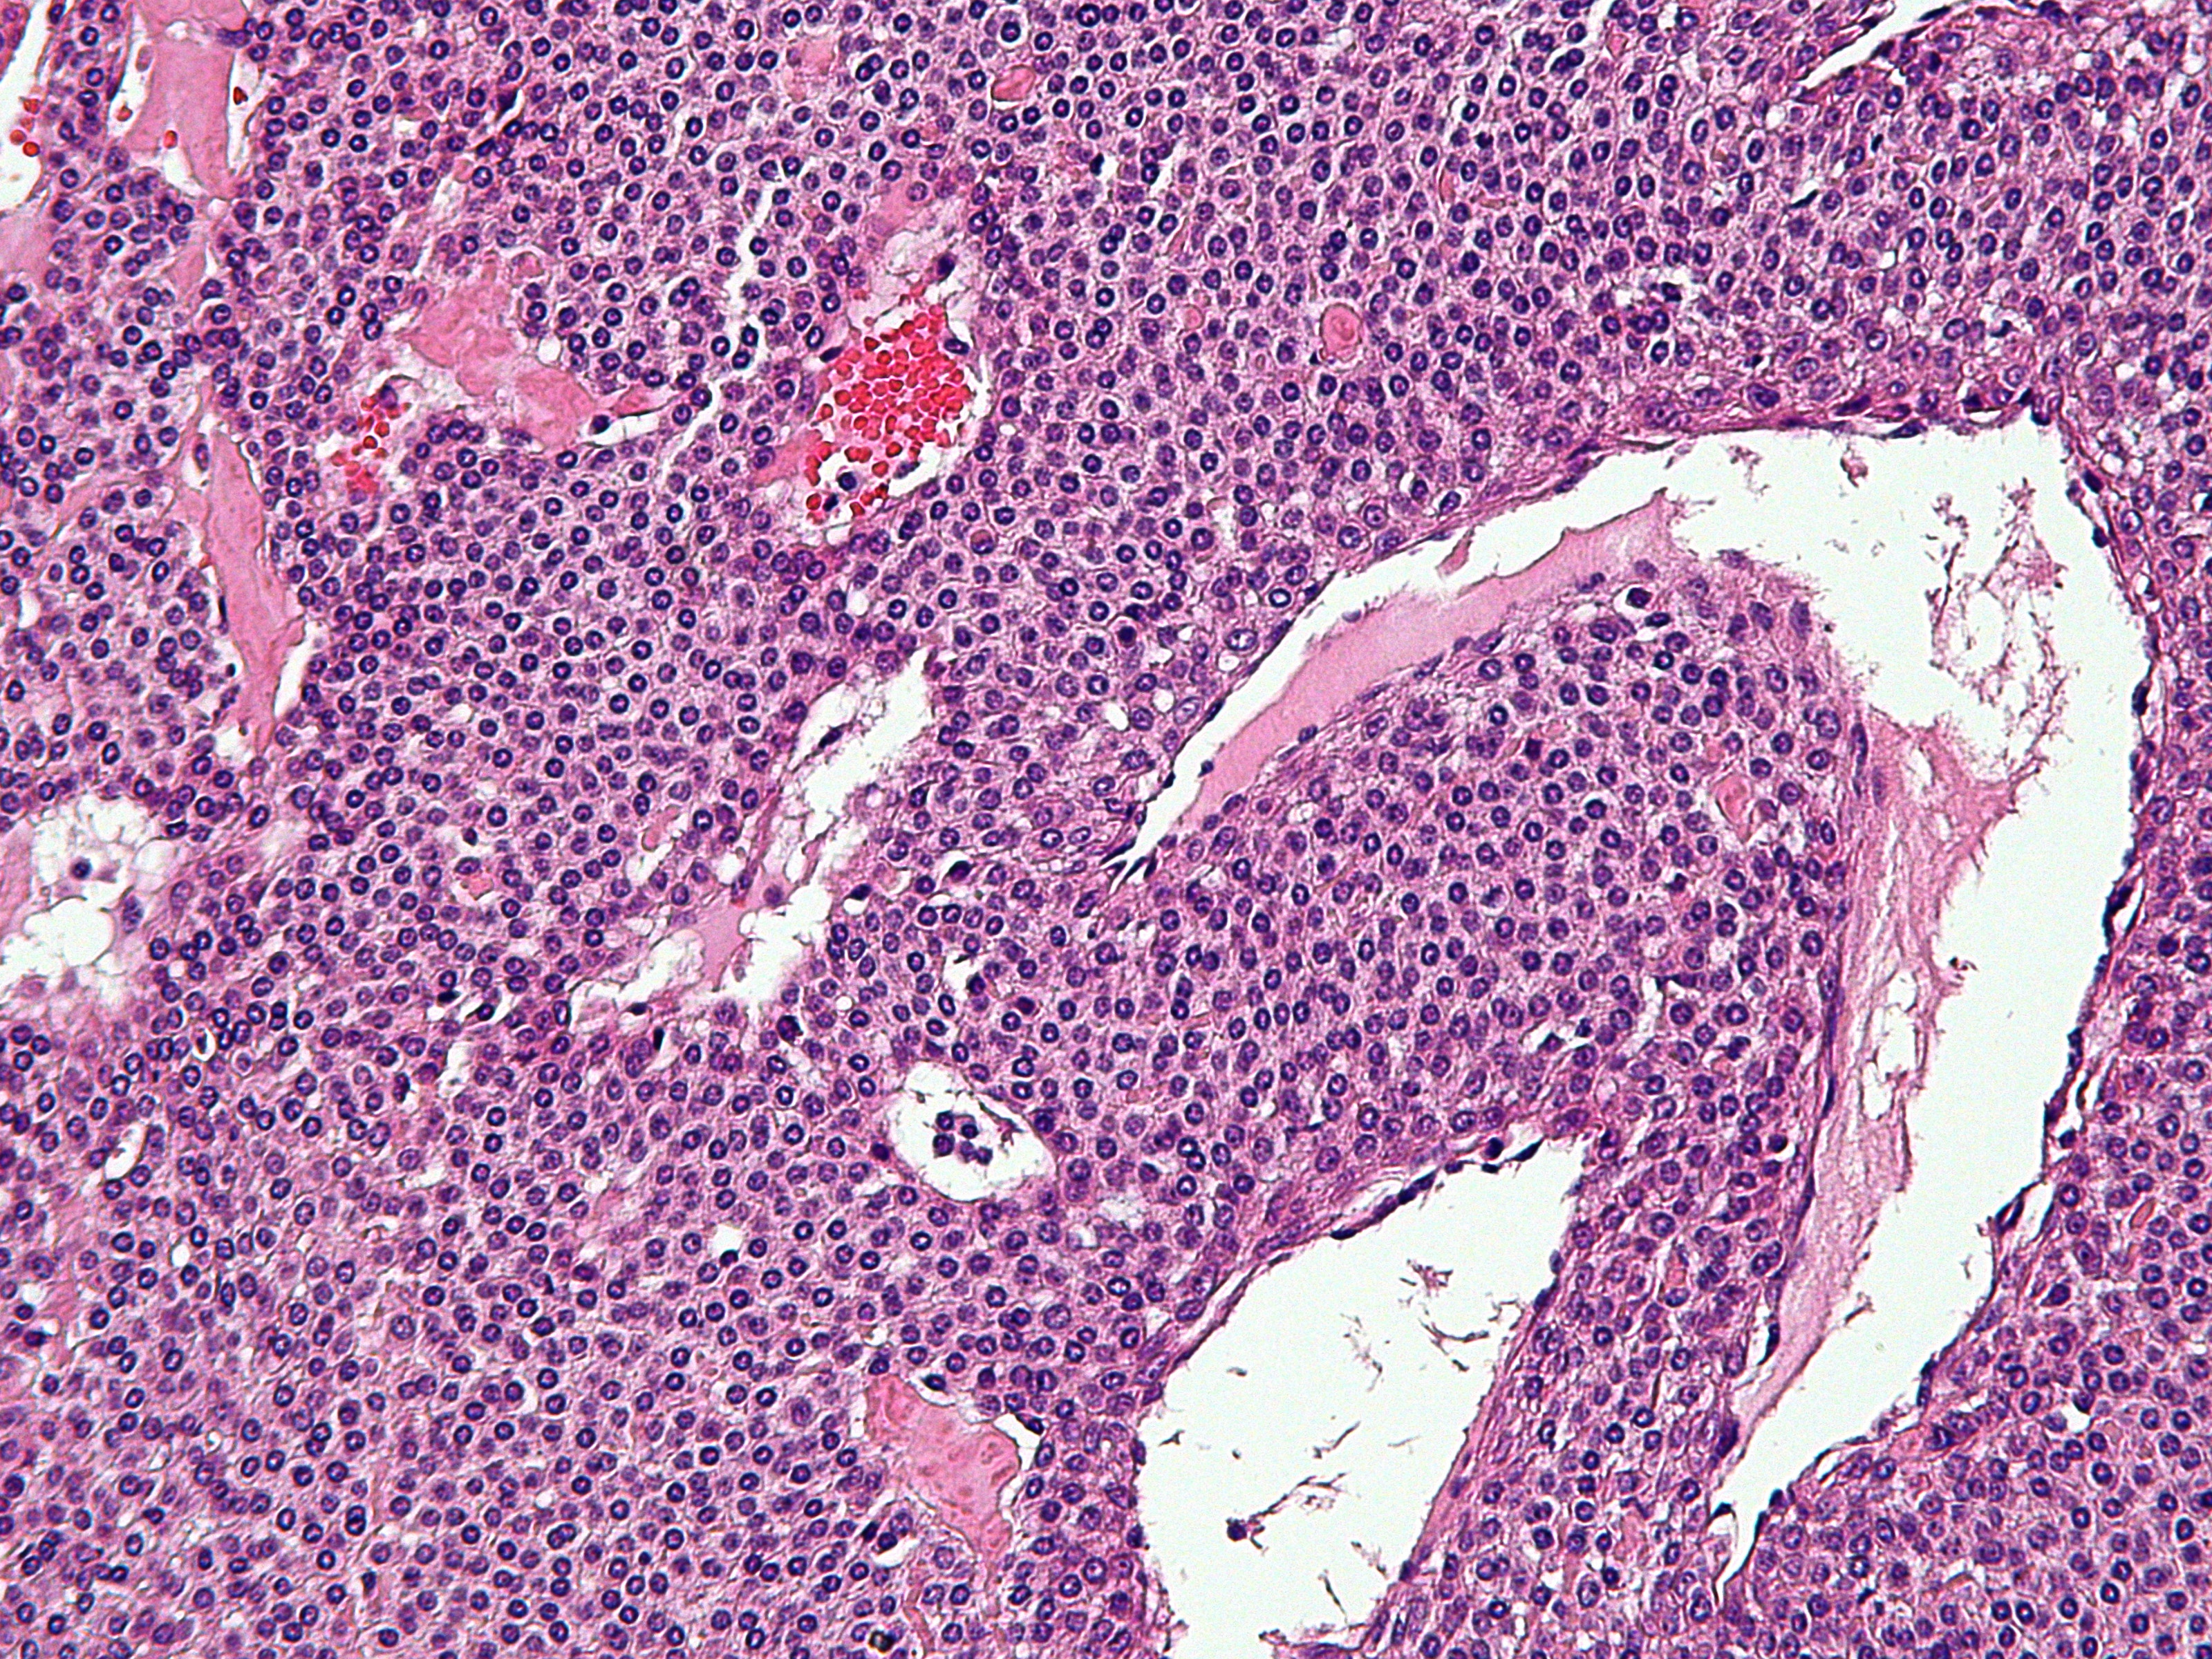

![Glomustumor (click on photo to enlarge) [source: Michael Bonert (Nephron) - Wikimedia - Creative Commons License 3.0] Glomustumor](../../../images/nail-disorders/glomustumor-5z.jpg) |

| glomus

tumor |

PA-Foto: Michael Bonert (Nephron) - Wikimedia (Creative Commons License

3.0).